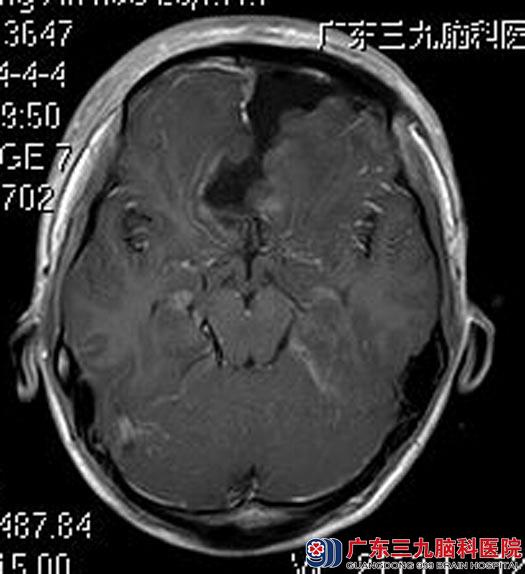

综合神经外科鲁明主任主刀,在全麻下行前颅窝底脑膜瘤切除术,术中见肿瘤呈灰白色,位于前颅窝底,质中,血供较丰富,双侧视神经被肿瘤压迫向后下方,用超声刀、电磁刀分块切除肿瘤,显微镜下全切,双侧颈内动脉及其分支、双侧视神经保留完整。手术后,小郑顺利出院。术后病理结果:脑膜瘤。

手术后